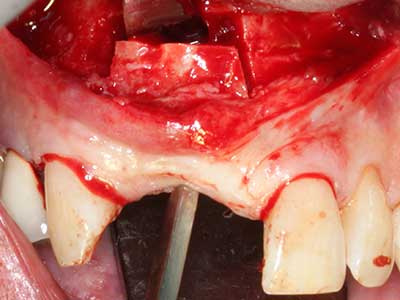

En la extracción de bloques óseos la piezocirugía también presenta ventajas adicionales: Además de la alta precisión en la osteotomía que ya se ha descrito antes, se ha comprobado que el uso de los delgados insertos de sierra resulta especialmente cuidadosas con el hueso. Frente a esto, sobre todo cuando se usan las fresas de Lindemann, cabe esperar pérdidas en la extracción significativamente más altas debido al mayor grosor de la parte frontal del cabezal (Lakshmiganthan, Gokulanathan et al. 2012). La separación basal que se necesita en particular en los injertos de bloque extraídos de forma retromolar se ve facilitada mediante sierras perpendiculares especialmente previstas a tal fin, lo que permite considerar que la cirugía piezoeléctrica es un procedimiento preciso y seguro para la obtención de bloques de hueso en el área retromolar (Happe 2007) (fig. 1-12).

Aplicación: Partición ósea / Cortical Split

El tejido óseo no solo tiene un contenido puramente mineral, sino que también presenta una importante proporción de fibras de colágeno. Esto no solo garantiza una buena resistencia a la presión, sino también una cierta flexibilidad, que puede aprovecharse para la realización de aumentos. En la plastia de expansión clásica a efectos de una partición ósea, la cresta maxilar atrofiada se divide en su eje longitudinal y, tras alcanzar una profundidad de osteotomía suficiente, se extiende con cuidado (fig. 13-16), en un caso ideal sin desperiostizar de forma visible el maxilar (Brugnami, Caiazzo et al. 2014, Stricker, Fleiner et al. 2014). Los sistemas de tornillos y placas con distancia de expansión creciente han demostrado su eficacia para distanciar entre sí las dos tablas óseas por debajo del umbral de rotura. Por regla general, se requieren anchuras de hueso residual de al menos 3 a 4 mm (Chiapasco, Zaniboni et al. 2006) para garantizar una flexibilidad y una cobertura ósea suficientes de los implantes que van a incorporarse. En caso necesario, una osteotomía de descarga vertical unilateral o bilateral puede mejorar la flexibilidad. Como alternativa a la técnica clásica se ha descrito una combinación con otras técnicas de aumento, sobre todo en la parte bucal.

Con el uso de sierras piezoeléctricas la división se efectúa de forma especialmente cuidadosa y sin pérdidas importantes de las dimensiones, por lo que no se han encontrado diferencias significativas entre los implantes realizados en el maxilar dividido y en la cresta alveolar no deficitaria (Chiapasco, Zaniboni et al. 2006, Danza, Guidi et al. 2009). No obstante, precisamente en la partición profunda y limitada de forma local, es preciso asegurarse de que exista una adecuada irrigación por agua para evitar que se produzcan sobrecargas térmicas en las áreas de osteotomía apical.